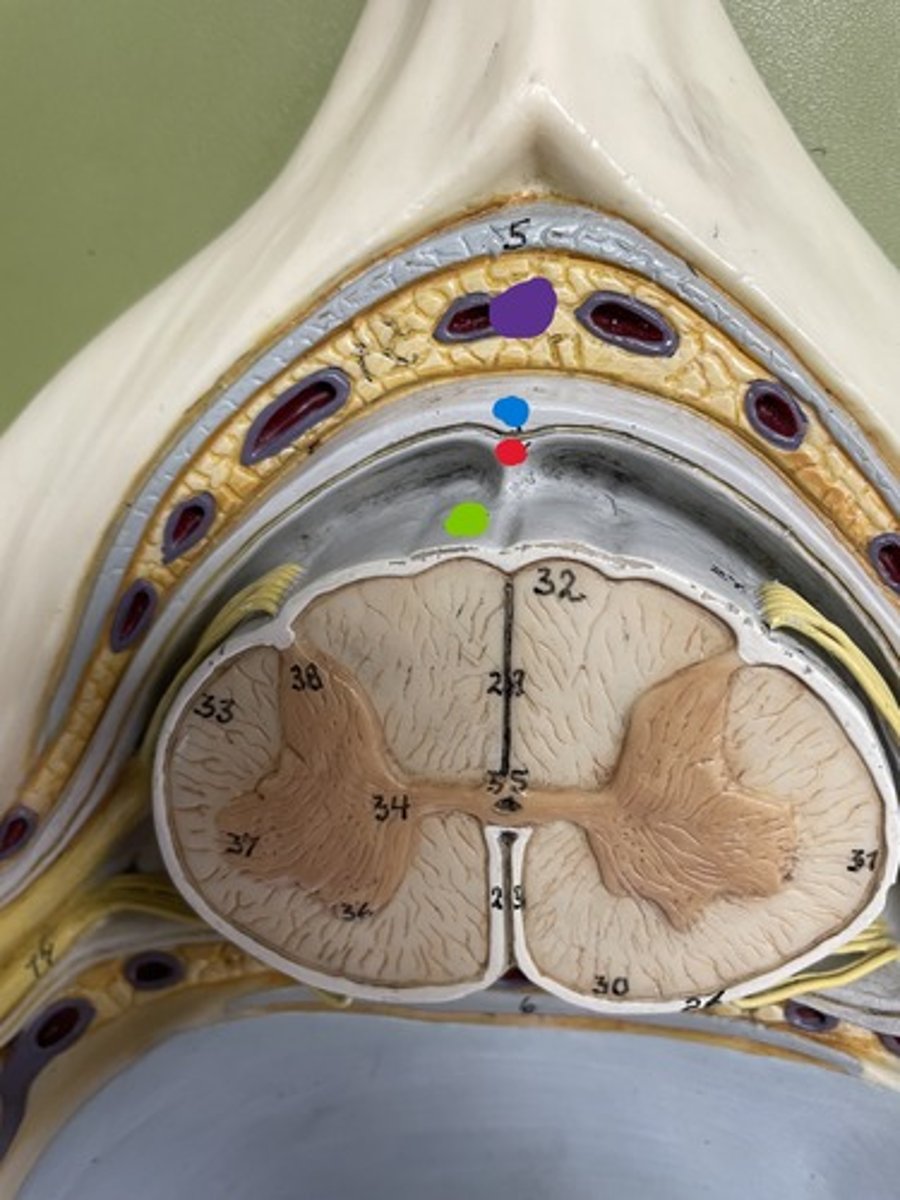

Dura mater

blue

Arachnoid mater

red

Pia mater

green

Epidural space

purple

Subdural space

between red and blue

Subarachnoid space

between red and green